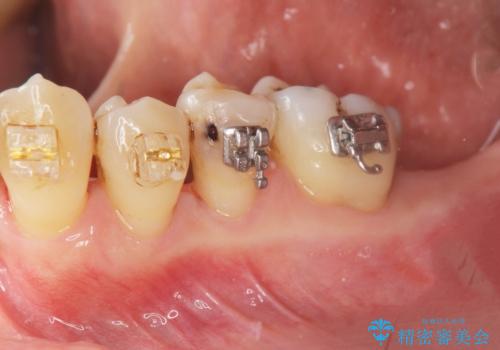

- 矯正装置

- 部分ワイヤー矯正

がたつきの強い天然歯を矯正治療で整えたのち、再生治療、歯周ポケットを除去する歯周外科手術を行いました。